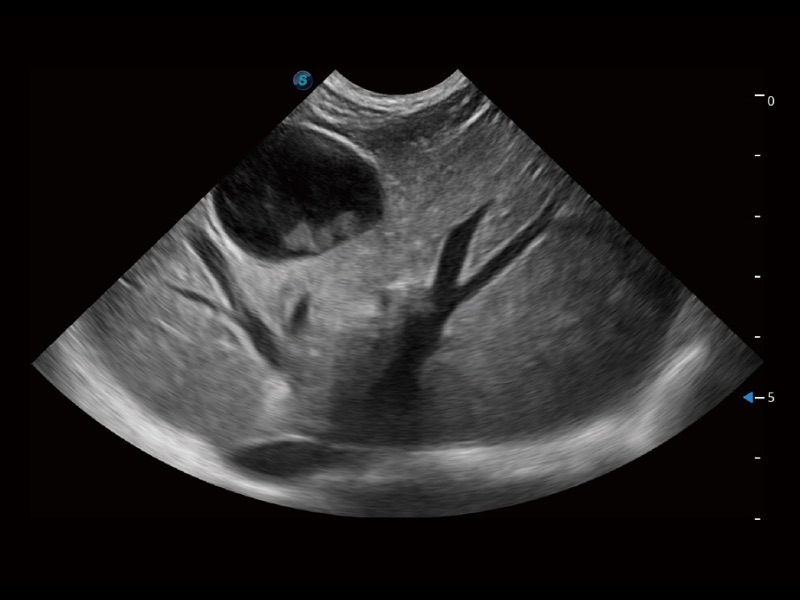

大型犬、马科、农场动物及大型异宠动物

ProPet 70专为动物医生设计,对不同的动物体型和生理结构作出了针对性的优化。通过动物影像专用软件,可满足个性化的应用需求,帮助动物医生获得更精确的诊断数据。

为精细结构及组织边缘提供高清晰度的图像和更大的成像视野。帮助减轻医生的用眼疲劳,快速精准获得测量的数据。